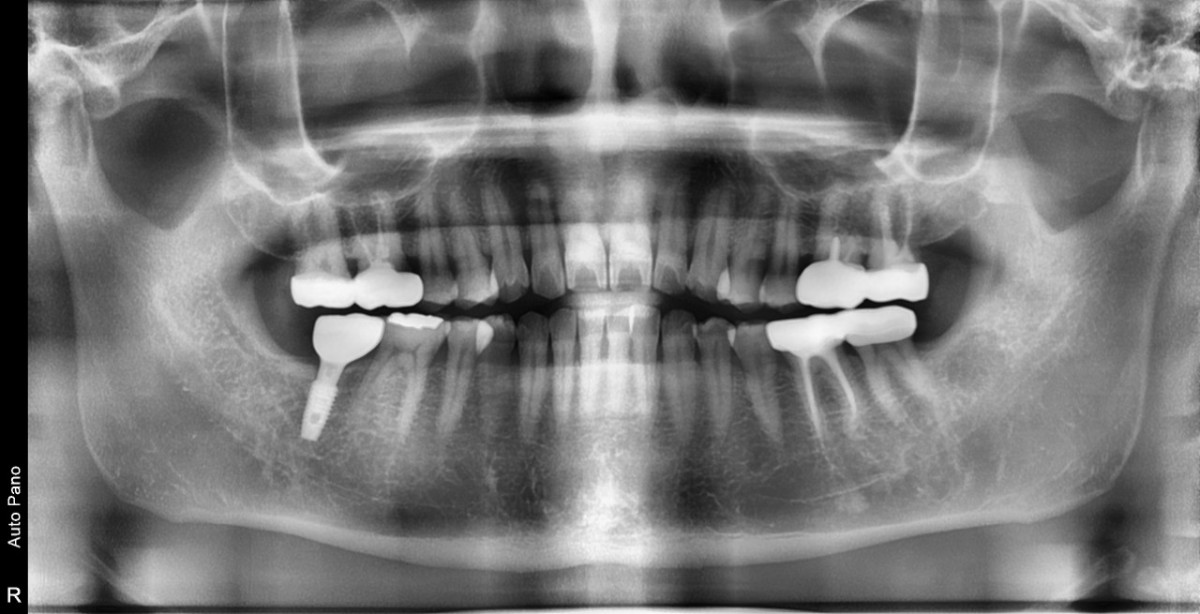

A 47-year-old male patient had a crown with an ill-fitting margin and crack-tooth syndrome in the lower 2nd molar. No systemic issue.

▲extraction